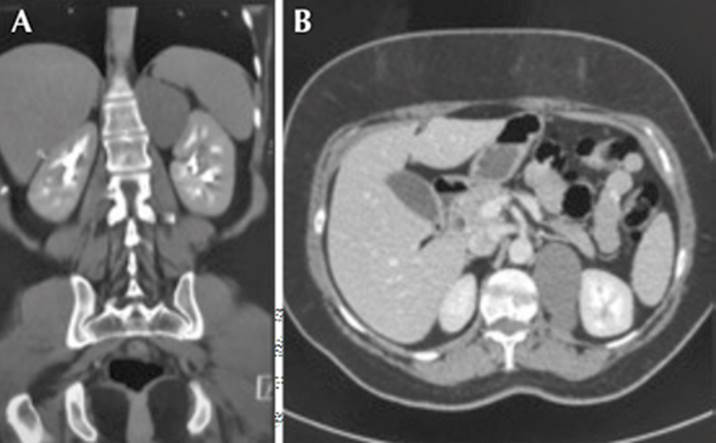

La urotomografía computada (UroTac) evidenció la glándula adrenal con masa de bordes bien definidos, de 7.1 x 4.3 x 6.0 cm, sin realce con la administración del medio de contraste (densidad promedio de 37 UH), sugerente de un quiste con contenido denso (Figura 1).

Figura 1 Urotomografía. Cortes coronal (A) y axial (B) que evidencian una masa de 7.1 x 4.3 x 6.0 cm en la glándula suprarrenal.